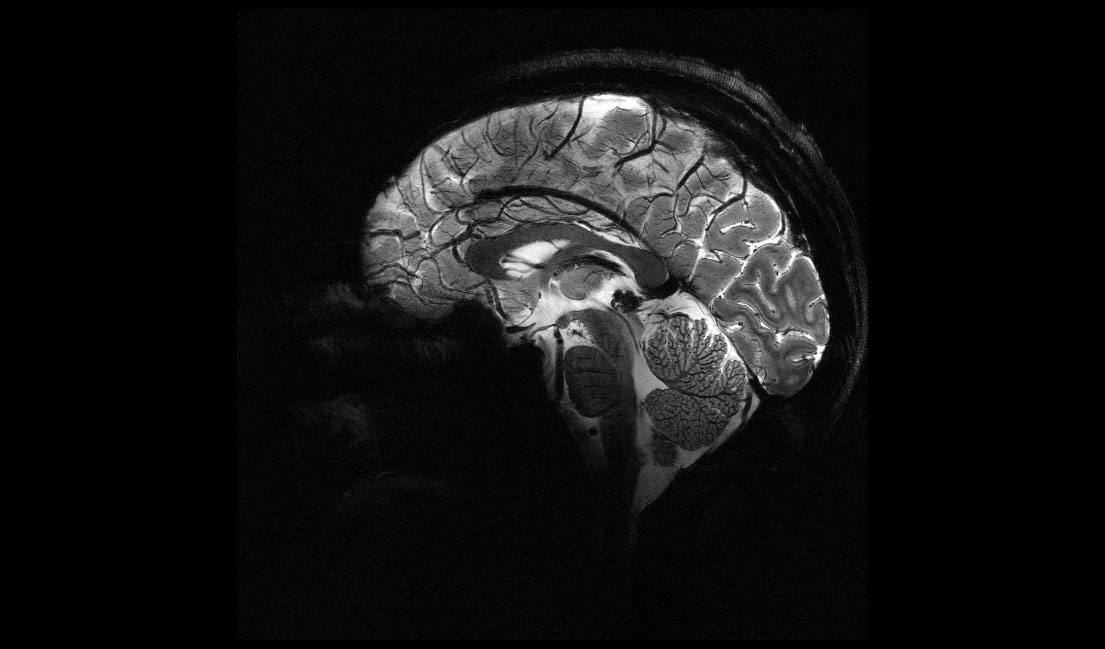

En avril 2024, une étape historique a été franchie : les premières images d’un cerveau humain obtenues grâce à l’IRM Iseult 11,7 teslas ont été dévoilées. Une prouesse scientifique et technologique, inédite avec un champ magnétique aussi élevé. Lors de cette conférence, Vincent Gras nous fera revivre l’aventure extraordinaire de ce projet hors norme : de sa conception au sein des équipes de l’IRFU du CEA jusqu’à son installation et sa mise en service à NeuroSpin, le centre dédié à l’imagerie cérébrale de pointe du CEA. Nous découvrirons les toutes dernières images produites par Iseult, comprendrons les principes qui se cachent derrière une IRM, et illustrerons les applications médicales et neuroscientifiques qu’ouvre ce nouvel instrument.